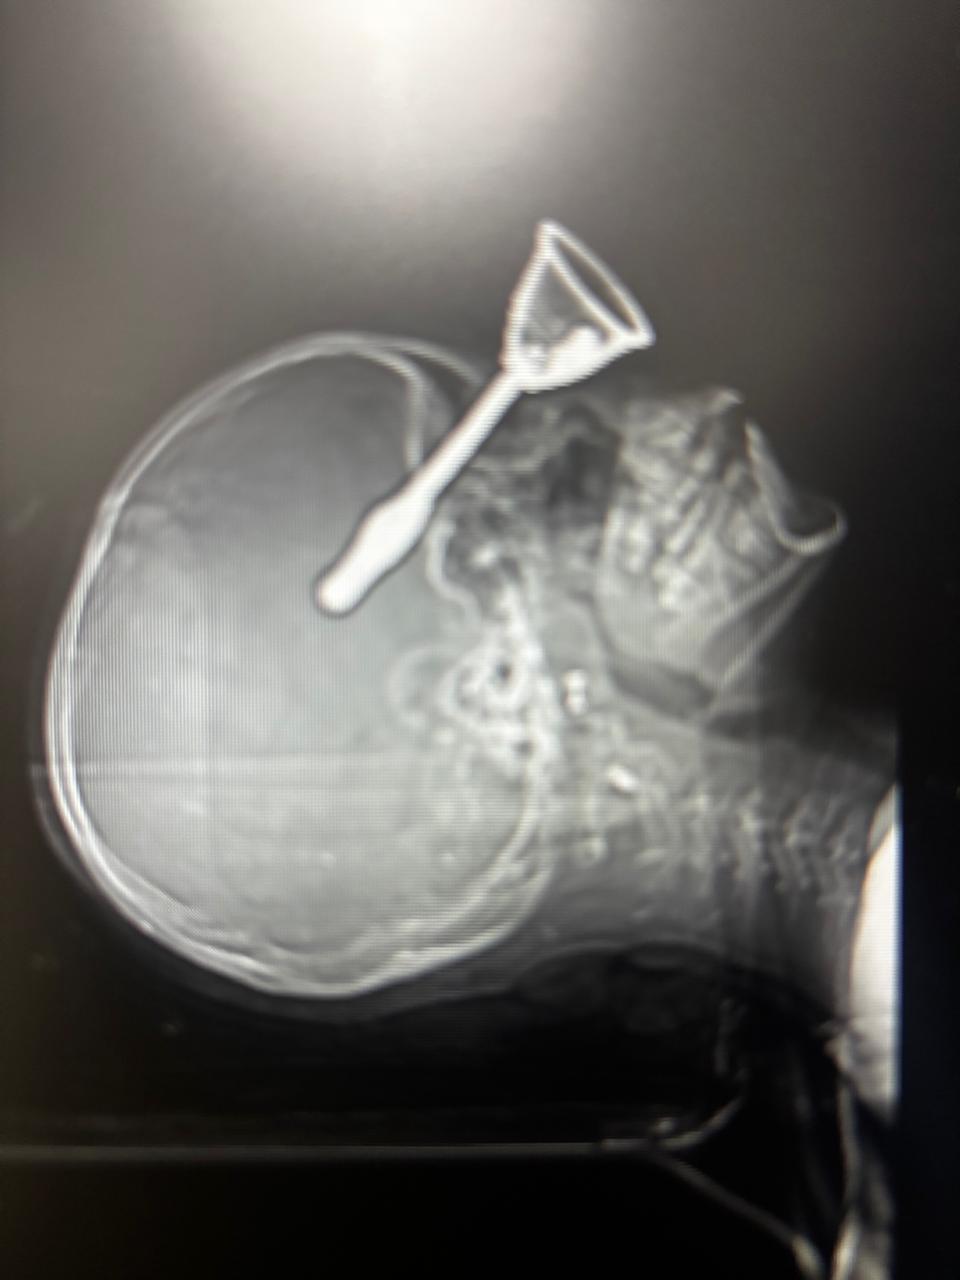

वहां एक्स-रे और सीटी स्कैन में पता चला कि घंटी का हैंडल आंख की हड्डी (Eye Orbit) पार कर ब्रेन टिशू (Brain Tissue) तक जा पहुंचा है। बच्ची की हालत गंभीर थी, इसलिए डॉक्टरों ने तुरंत उसे रायपुर के डीकेएस अस्पताल रेफर कर दिया।

घंटी का हैंडल लगभग 4 से 5 सेंटीमीटर दिमाग के अंदर तक घुसा हुआ था। ऑपरेशन बेहद चुनौतीपूर्ण था। डॉक्टरों को हर मिलीमीटर पर सटीकता रखनी पड़ी। आखिरकार घंटी का हिस्सा सुरक्षित रूप से बाहर निकाला गया। इसके बाद डॉक्टरों ने दिमाग की बाहरी परत (Dura) को रिपेयर किया।